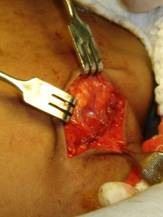

Foram solicitados exames imaginológicos (raidiografia norma lateral oblíqua da mandíbula, PA de face com a finalidade de detectar possível cálculo salivar) e também ultra-sonografia com a finalidade de avaliar os limites e tamanho real da lesão. (FIGURA 2)

clip_image005[5]

Ultra sonografia demonstrando lesão expansiva arredondada na glândula submandibular direita com aspecto de neoplasia.